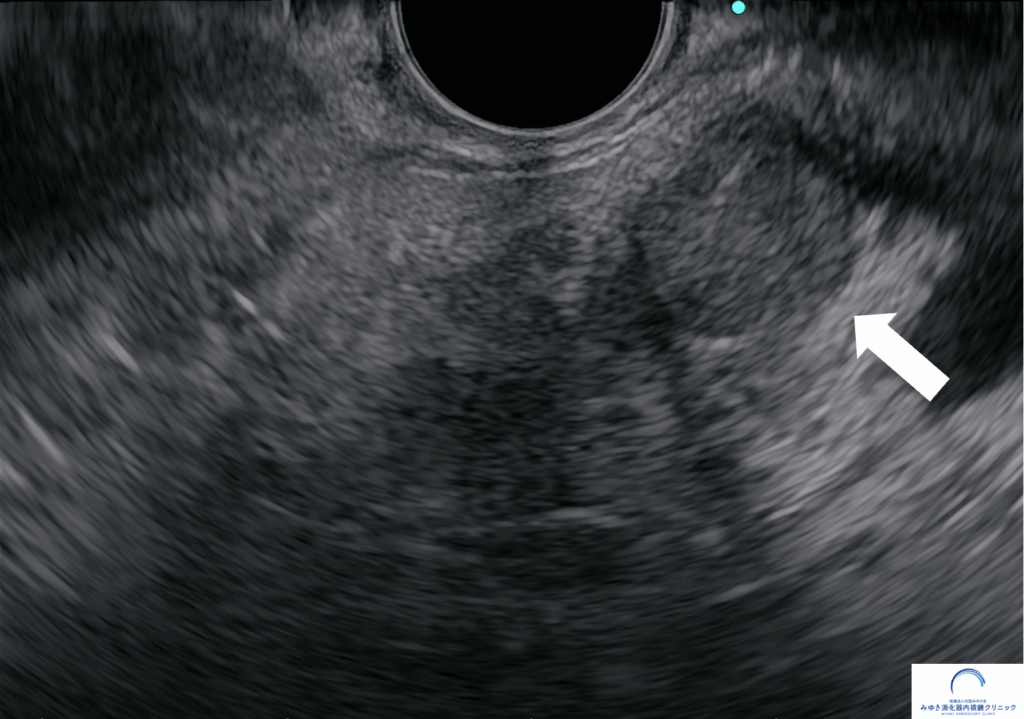

<ステージ1膵がん>

膵嚢胞、膵管拡張精査目的に当院で超音波内視鏡を行いました。膵臓に10mmの腫瘤を認めたため、超音波内視鏡穿刺吸引法(EUS-FNA)を施行し、膵がんと診断しました。CTとMRIではこの腫瘤は同定できませんでした。